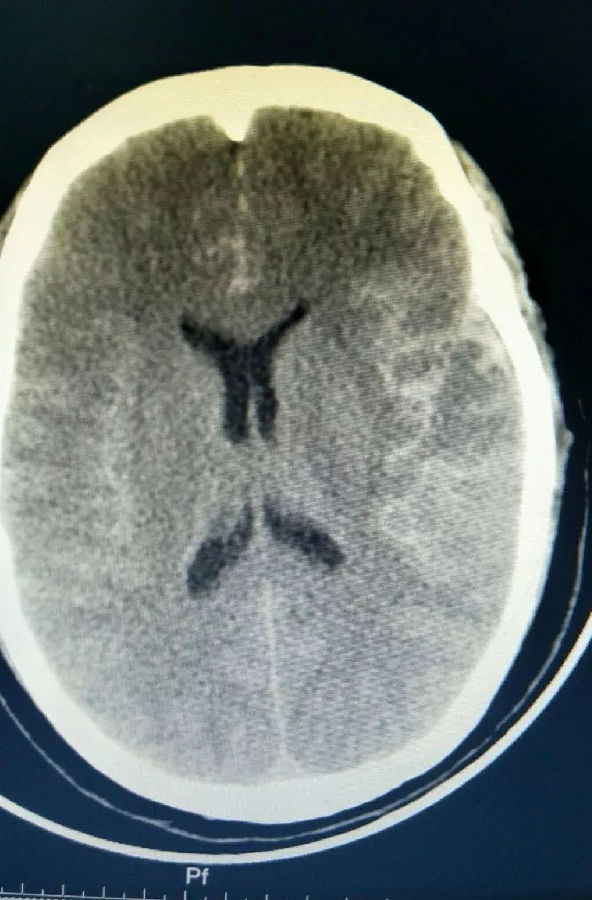

▲术前CTA显示右大脑中动脉动脉瘤

经64排CT血管造影进一步确诊,患者为颅内右外侧裂血肿,蛛网膜下出血。李要辉及时将造影显示的图像发给谭占国教授查看,远程接受治疗指导。